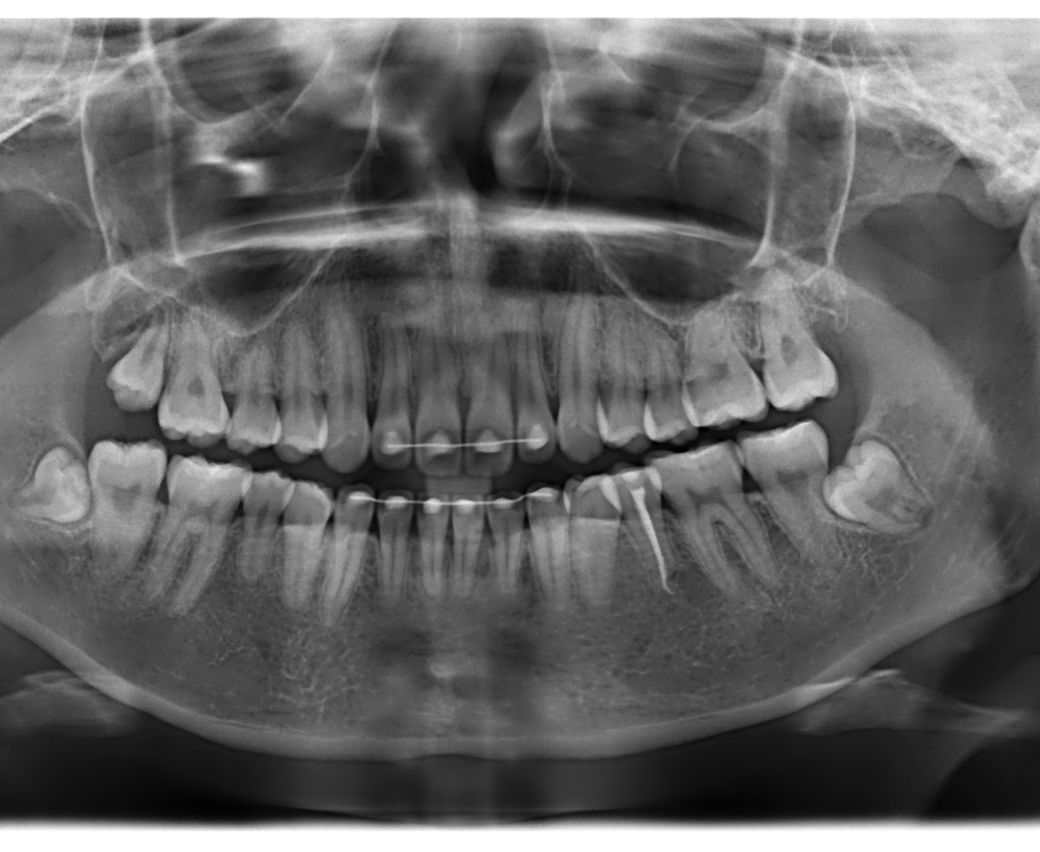

사진상 왼쪽 위에 어금니가 선천적으로 없습니다. 교정치과에선 사랑니가 잘 나오면 대체해서 쓰라고 하셨습니다. 이번에 사랑니 발치 치과를 가니 염증 유발성이 있어 발치하는게 좋겠다고 뽑으셨고 어금니 임플란트 추천을 해주셨습니다. 제가 엑스레이 보기엔 사랑니가 잘 내려오고 있는 편인거 같은데 의사 전문가 입장에선 어금니 대체가 불가능한 치아 상태였나요? 이미 뽑아버렸지만 제 치아를 사용할 수 있는 기회였는데 아깝기도 하고 궁금해서 여쭤봅니다 (사진 순서는 뽑기 전, 후 입니다) 그리고 꼭 임플란트를 해야 할까요? 씹는 것엔 불편함이 없습니다

• 1번 째 사진

• 사랑내가 정상적으로 맹출이 되었다면 자연치아처럼 쓸 수 있습니다. 사진에 보이는 사랑니의 경우엔 치아 풀이가 짧고 교합력을 담당하기에는 약해 보입니다. 통증이나 불편감이 없다면 사용할 수 있지만 사랑니가 약해서 교합력을 지탱해주지 못한다면 발치를 해주는 것이 좋을 수 있습니다. 자세한 확인을 위해서 치과에서 진료를 받아보세요

• 교정을 동반하여 해당 사랑니 부위를 조금 더 정출시키고 크라운을 했다면 어금니처럼 사용할 수도 있습니다. 다만 현재 사진만으로는 정확히 사랑니의 상태를 판단하기 어렵습니다. 어금니가 앞 뒤 그리고 좌 우로 어떻게 되어 있느냐에 따라서 어금니처럼 사용하지 못할 수도 있습니다.

1. 사진상 위치와 방향은 괜찮으나 주변 치주인대의 양상이 정상적이진 않습니다